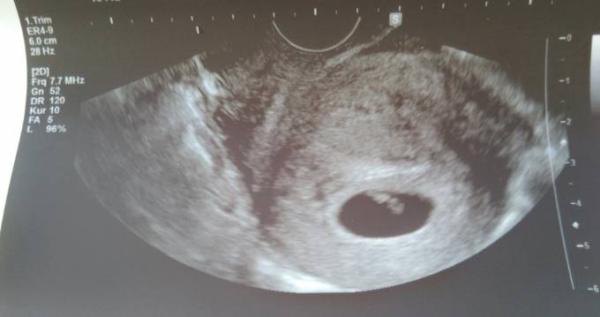

Aber ich wollte auch sagen das wir heute den ersten Termin beim FA hatten und wir unseren Krümmel sehen durften.

Die Ärztin meinte das alles super aussieht und das das kleine Herzchen schlägt und somit das wichtigste erstmal geschafft. Der Kontakt zur Mama.

Ich konnte es nur mit genauen hin schauen sehen weil es kleiner Eckenhocker ist wie die Ärztin meinte.

Bin heute 6 + 3